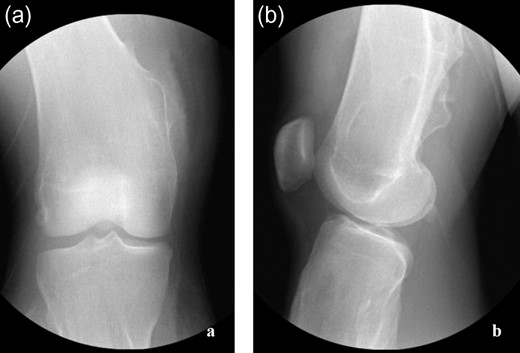

The patient is an 18-year-old female with history of MHE with many osteochondromas throughout her lower extremities who presented with acute right medial knee pain and inability to extend her knee, locked in a flexed position. The patient reports squatting in deep flexion when she felt a pop on the medial aspect of her right knee resulting in an acute inability to actively, passively or forcefully extend her knee past 90° of flexion. She has a remote history of fracture involving a right medial proximal tibial osteochondroma that has since healed uneventfully. On examination, there was tenderness localized to the medial hamstrings and soft tissues around her medial proximal tibial osteochondroma. Neurovascular function was intact. Forced knee extension could not overcome the locked knee joint and caused significant pain over the medial proximal tibia and along her hamstrings. Her patella–femoral joint was well-aligned, and she was non-tender over the anterior knee nor the medial/lateral joint lines. She had no knee effusion. Initial radiographs (Fig. 1a–c) confirmed multiple lower extremity osteochondromas, notably with a large, pedunculated osteochondroma at her right medial proximal tibia, well-healed since her previous fracture. No advanced imaging studies were performed as clinical concern for intra-articular pathology was low and patient positioning prohibited. Assessment was a locked knee secondary to incarcerated hamstring tendons around her longstanding right medial proximal tibial osteochondroma. Operative intervention was planned for excision of the osteochondroma and exploration of the soft tissues.

(a–c) Presenting radiographic images with knee locked in flexion.